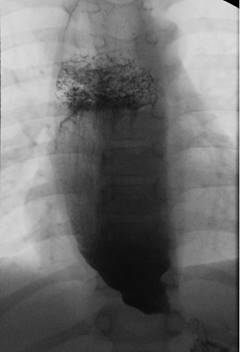

Para confirmar este diagnóstico se realizó estudio radiológico con bario que evidenció un esófago distendido con aumento del calibre, nivel líquido-líquido, restos de alimentos y en su sector distal disminución del calibre con terminación en “pico de pájaro”, vaciamiento por gravedad no observado en decúbito acompañado de contracciones peristálticas no efectivas (Figura 2). Posteriormente se realizó una fibrogastroscopia (FGC) y toma de biopsia que evidenció elementos de esofagitis leve. No fue posible la realización de la manometría esofágica. Para la valoración de etiologías secundarias la tomografía descartó imágenes sugestivas de compromiso extraluminal como tumores o conglomerados adenopáticos y patologías propias de la pared esofágica. Se realizó serología para Trypanosoma cruzi, por ser procedente de zona endémica, la cual fue negativa.

Figura 2 Estudio radiológico de esófago con bario: esófago distendido, aumentado de calibre, con nivel líquido-líquido. Sector distal con terminación “en pico de pájaro”.